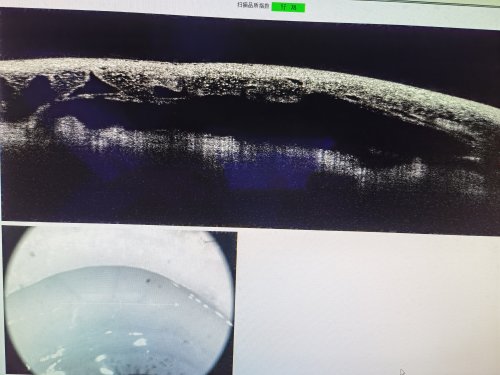

右眼视神经OCT